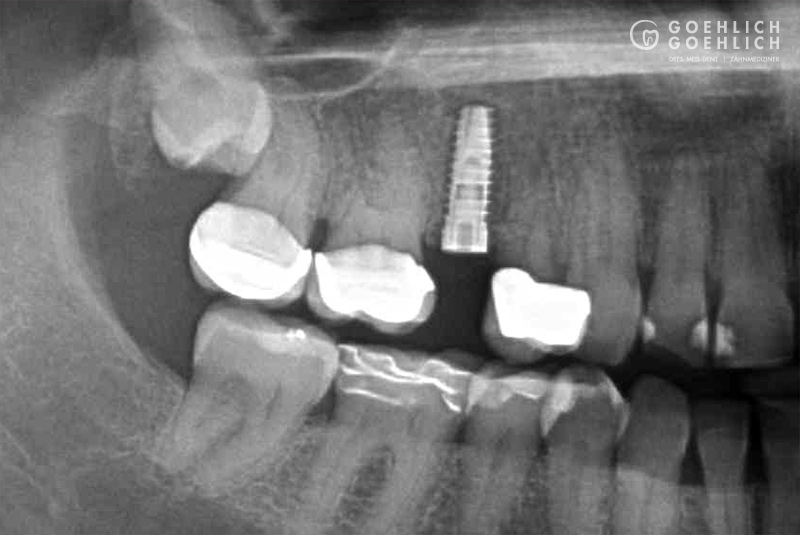

Mittels digitaler Volumentomographie (DVT) sind wir in der Lage, die knöcherne Ausgangslage vor Implantation dreidimensional darzustellen. So können die genauen Lagebeziehungen zu Nerven oder auch zur Kieferhöhle optimal bestimmt werden.